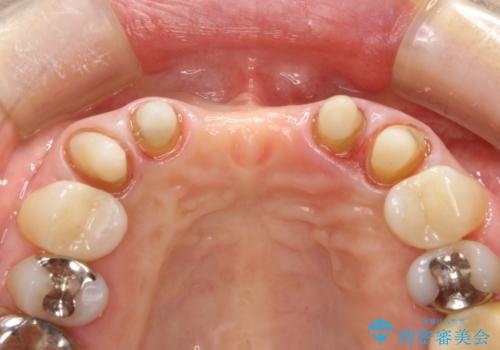

- 仮歯の製作、古い土台(メタルコア)の除去まで行い、根管治療は専門医に依頼

→根管治療終了後、ファイバーコアを築造し、新しいセラミックブリッジを製作した。